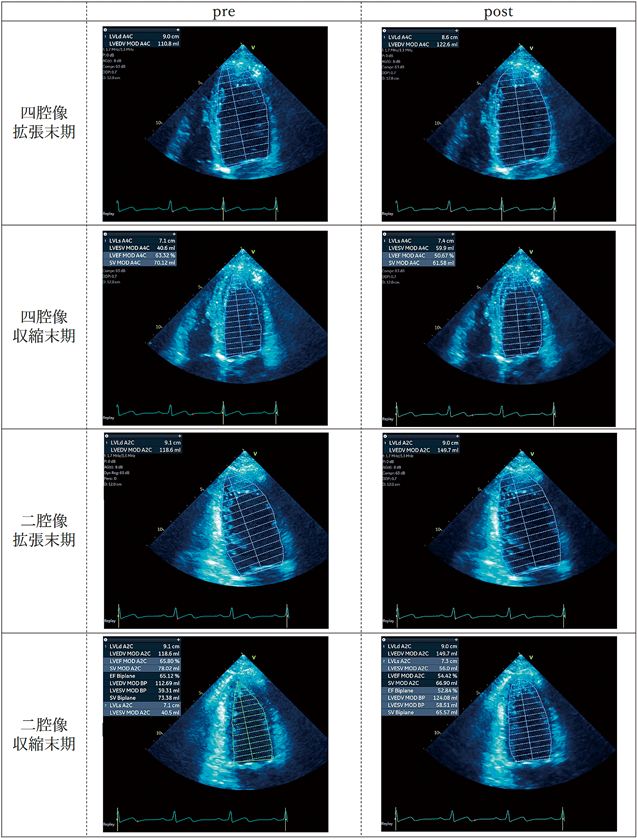

実践3D心エコー図法